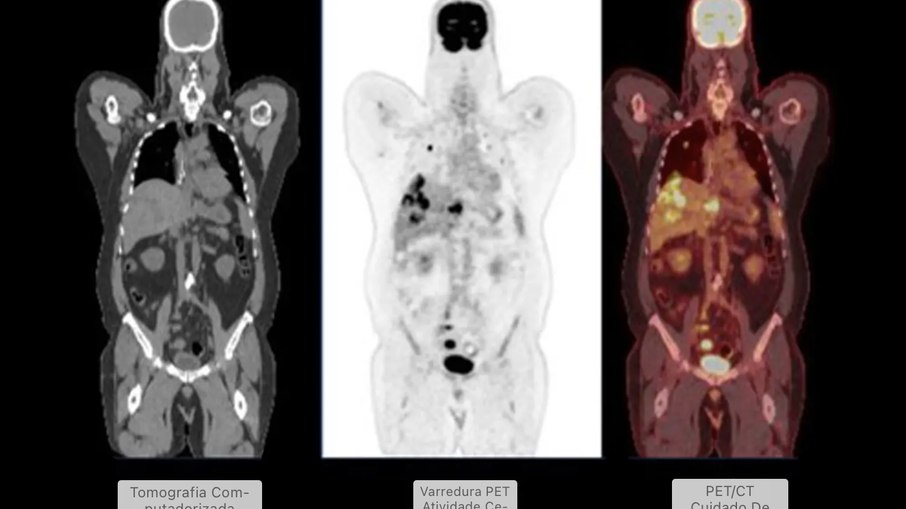

A questão é que o mecanismo de ação desses medicamentos também pode afetar como o corpo absorve o marcador radioativo FDG, usado nas tomografias PET. Esse marcador identifica células com metabolismo acelerado, como as cancerígenas. Quando o padrão de absorção é alterado, os exames podem mostrar “pontos quentes” enganosos, fazendo parecer que há inflamação ou tumor onde não existe.

Os médicos usam PET-CT para diagnosticar câncer e doenças inflamatórias, além de monitorar os efeitos do tratamento